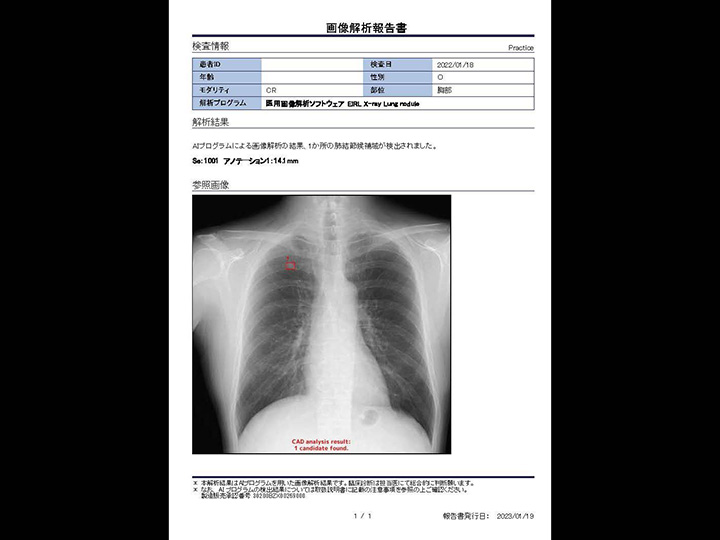

胸部CR×肺結節

EIRL Lung Nodule

胸部X線画像より、肺結節の形状に類似した領域を検出します

- クリニックで、ワンマン読影の補助として

- 検診で、膨大な読影の見落とし防止として

- 病院で、胸部が専門ではない診療科の先生の補助として

エルピクセル株式会社より提供を受けている医療機器「医用画像解析ソフトウェア EIRL X-ray Lung nodule」を搭載しております。